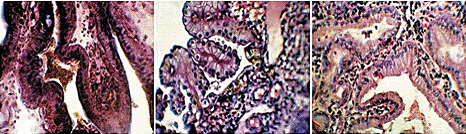

Далее пролиферирующий эпителий эндометрия превращается в секреторный. И наступает гестагеновая фаза, которая может быть разделена на три периода ранний, промежуточный и поздний. В ранний период секреторной фазы ядра эпителиальных клеток маточных желез находятся возле парабазальной мембраны, но под ними образуется большое количество вакуолей. Затем вакуоли перемещаются к апикальной мембране и вытесняют ядра к базальной мембране. Они вновь выстраиваются в один ряд вдоль базальной мембраны. Но апикальный край желез уже не такой ровный, через него начинается секреция. Просвет желез расширяется, в нем обнаруживается секрет маточных желез (рис. 9).

На пике активности маточных желез в среднюю стадию фазы секреции клетки маточных желез становятся больше похожи на кубические, в просвете желез много секрета, ядра занимают центральное положение в клетке (рис. 10). Наконец в позднюю стадию секреции, при не наступившей беременности активность желтых тел начинает снижаться, и клетки желез становятся уплощенными, но еще продолжают секретировать, секрет обнаруживается в просвете желез (рис. 11). По мере снижения прогестероновой активности секреторные процессы в них затухают, и эндометрий подвергается обратному развитию, постепенно принимает вид, показанный на рис. 12, 13. Железы еще имеют много извилин, просвет их расширен, но эпителий в них плоский. Резко снижается клеточность стромы эндометрия. Затем эндометрий принимает первоначальный вид (рис. 4, 5).

Причина: Типичная пиометра предположительно вызывается первичными инфекционными процессами. Примерно в конце эструса или начале проэструса бактерии поднимаются через открытую шейку матки в матку и вызывают воспаление. Повышение уровня прогестерона вызывает закрытие матки и одновременно уменьшает устойчивость эндометрия к бактериальным инфекциям. Количество бактерий в матке увеличивается, и возникает эндометрит с гиперсекрецией маточных желез. Постепенно матка наполняется гнойным секретом. Токсины из содержимого матки всасываются, и это приводит к токсемии. Острая фаза воспаления протекает клинически незаметно, фаза токсемии может проявляться различным образом. При анализе содержимого матки собак, страдающих пиометрой, обнаруживаются преимущественно неспецифические бактерии (главным образом, Е. coli, однако также и стафилококки, клебсиеллы, пастереллы и др, бактерии) (рис. 14a, 14b, 15).

В редких случаях пиометра может развиваться как осложнение при прерывании беременности в стадии нидации с помощью эстрогенов (особенно при начале лечения позже l5 дня течки) или после сдвигания течки с помощью гестагенов продленного действия. После долгосрочного подавления половой функции с помощью гестагенов у сук чаще наблюдается мукометра (накопление в матке бактериологический стерильной слизи) (рис. 16а, 16b)

Закрывается канал шейки матки. А железы эндометрия начинают интенсивно продуцировать секрет, который скапливается в полости матки. Если при этом содержимое матки имеет водянистый характер, то болезнь называют водянкой матки, или гидрометрой (рис. 17), если слизистый - миксометрой. При значительном скоплении микробов из слизистой оболочки в жидкость мигрируют в большом количестве лейкоциты. Это ведет к гнойному распаду задержавшихся в полости матки выделений, развивается пиометра (рис. 18а, 18b). Накопление гнойных масс в полости матки может быть настолько велико, что стенки органа не выдерживают внутреннего давления и разрываются. Происходит излияние гноя в брюшную полость, что приводит к диффузному перитониту. Прободение стенки матки может произойти и вследствие гнойного расплавления тканей.